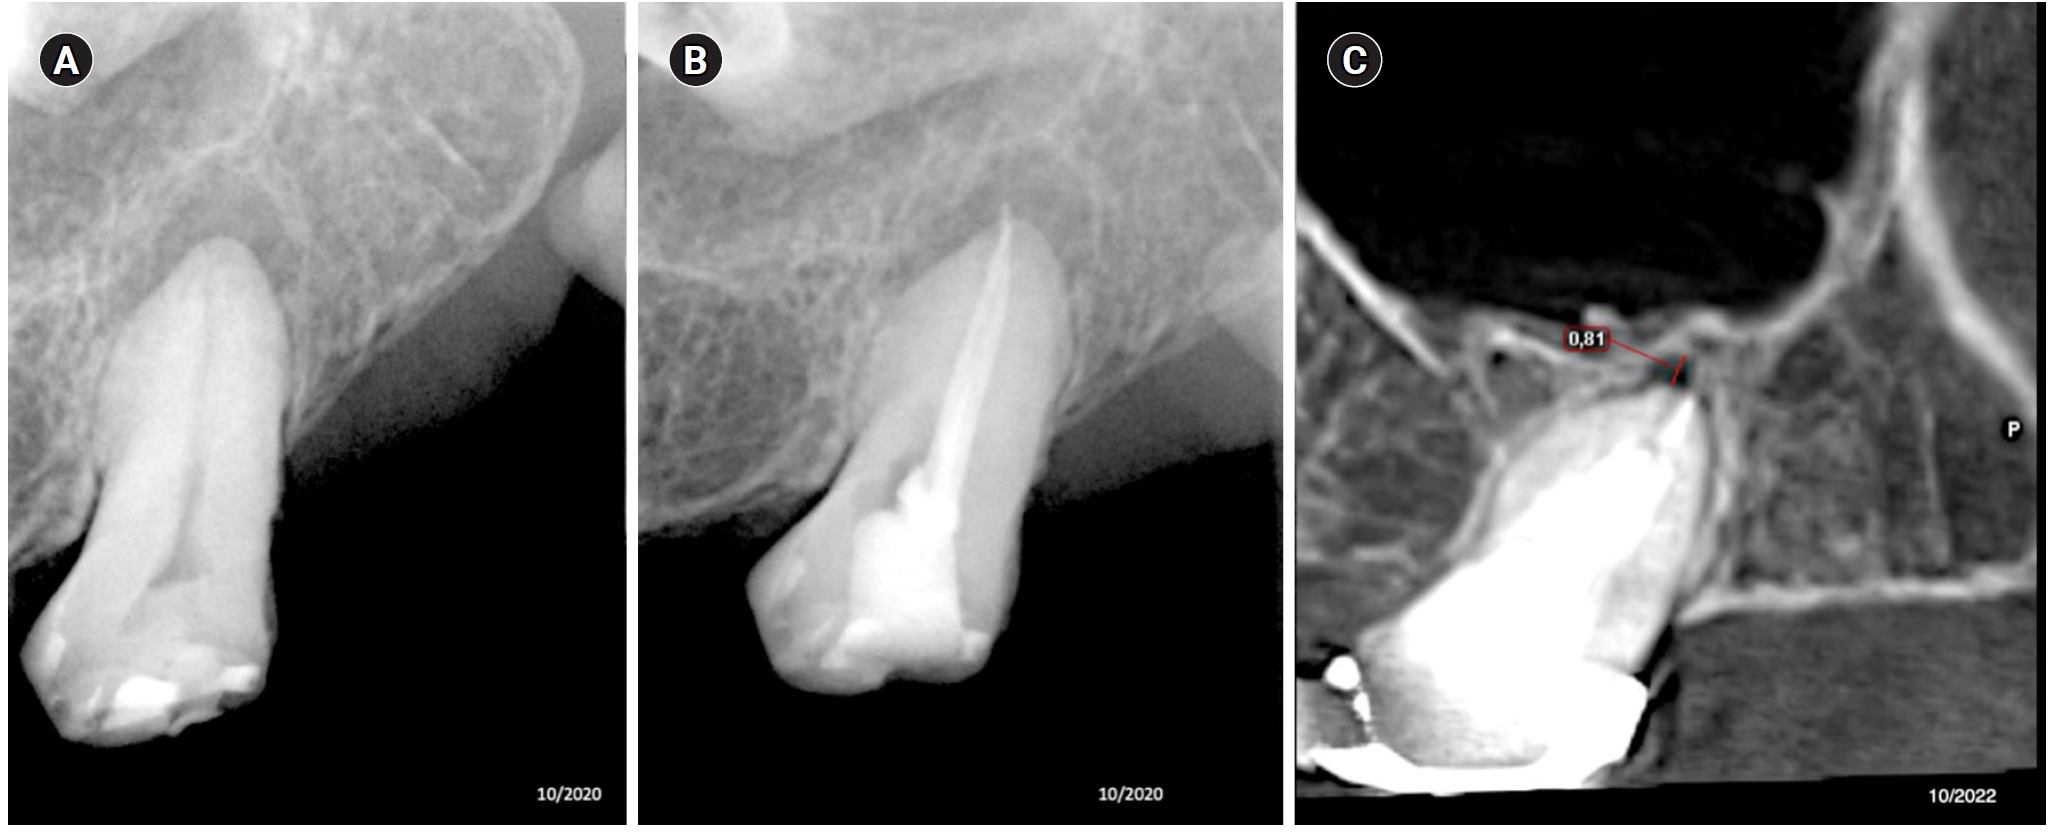

This image shows tooth 27 diagnosed with pulp necrosis and asymptomatic apical periodontitis. (A) Diagnostic X-ray. (B) Immediate after obturation. (C) Tomographic control where an apical image in the process of healing is observed after 24 months.